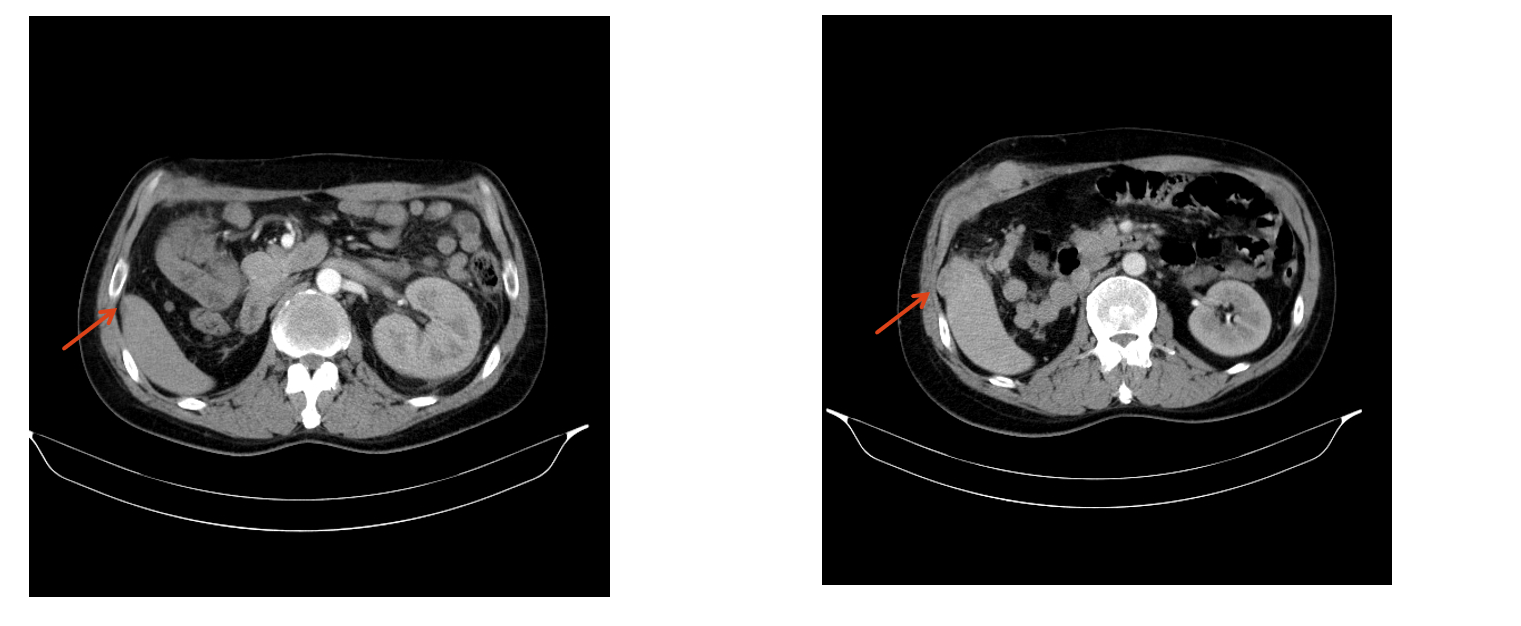

患者一月余前检查时发现右肾肿瘤,伴有肉眼血尿,尿频,尿急,尿痛,伴有腰痛,无发热等其他特殊不适,于当地医院超声检查提示右肾占位性病变,考虑肿瘤,为求进一步诊治于我院就诊,行肾脏增强CT检查提示右肾肿瘤,考虑肾透明细胞癌可能性大,肿瘤突破被膜,肾周受侵。病程中饮食睡眠欠佳,体重减轻近10kg。

右肾肿瘤 9.8cm*7.9cm

肾周受侵

肾门可见肿大淋巴结

未见明显远处转移

右肾肿瘤(肾透明细胞癌可能极大)III期 T3NxM0 IMDC 中危组。